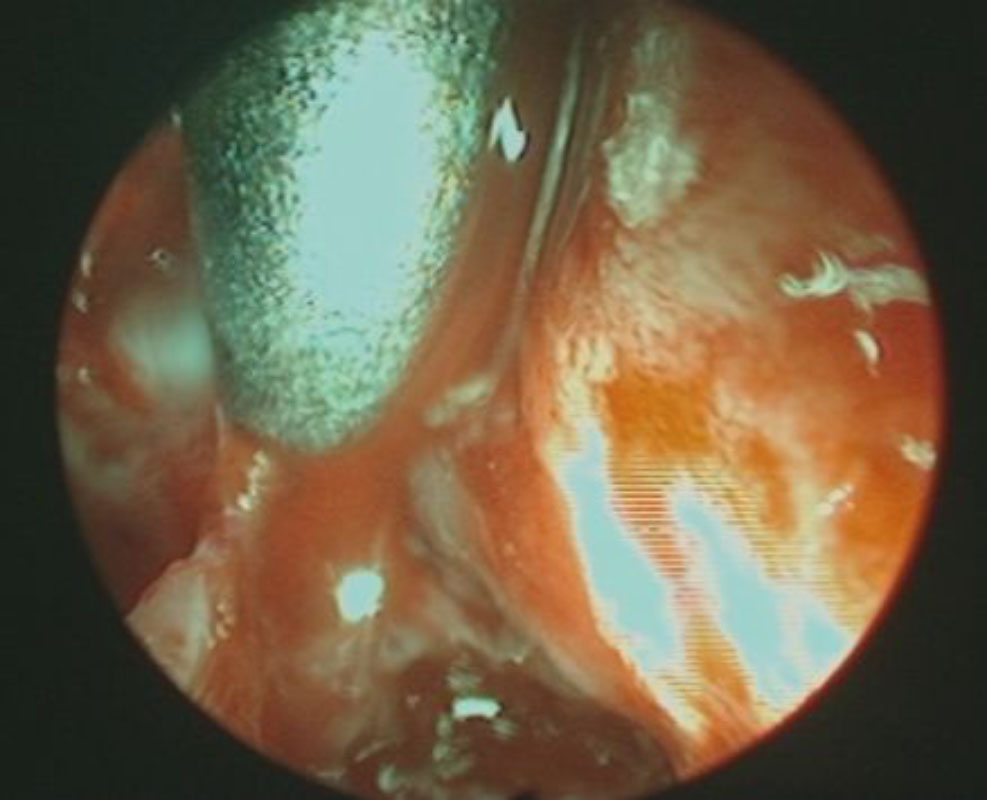

術中写真

摘出 前

摘出 中

摘出 後